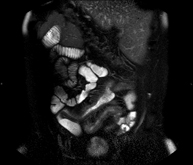

- Entero-RM

Prueba diagnóstica no invasiva que consiste en la obtención de imágenes de alta definición anatómica del intestino mediante el empleo de un campo electromagnético y ondas de radio (con un emisor y un receptor). No utiliza radiación ionizante. Normalmente requiere el empleo de contraste paramagnético (Gadolinio). Está indicada principalmente en el diagnóstico, seguimiento y control de respuesta al tratamiento de los pacientes con Enfermedad de Crohn.